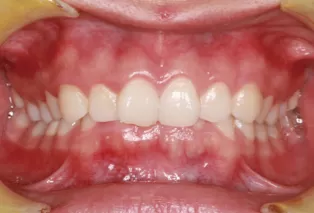

Intraoral photos